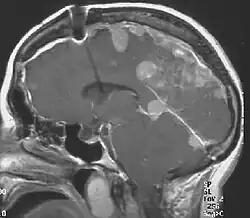

![]() | |

| Figure of various morbidities associated with neurofibromatosis type II[1] | |